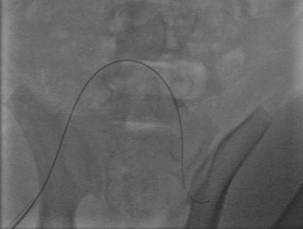

Qualitative Results. Fig. 5 illustrates the catheter and guidewire segmentation results of fine-tuning ViT on our method and different foundation models. The visualization portrays that our method excels in accurately delineating the catheter and guidewire structures, showcasing superior segmentation performance compared to other approaches. This figure further confirms that we can successfully train a federated endovascular foundation model without collecting users’ data and the trained foundation model is useful for the downstream segmentation task.

|

Animal |

Phantom |

Simulation |

Input

Ground Truth

LVM-Med

SAM

CLIP

Ours